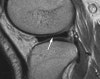

MRI : 반월상 연골 손상을 진단할 수 있는 가장 좋은 방법으로 알려져 있지만 원판형 연골을 진단하는데 있어서의 MRI의 역할에 대해서는 논란의 여지가 있습니다.

MRI : 원판형 반월상 연골(Discoid meniscus)